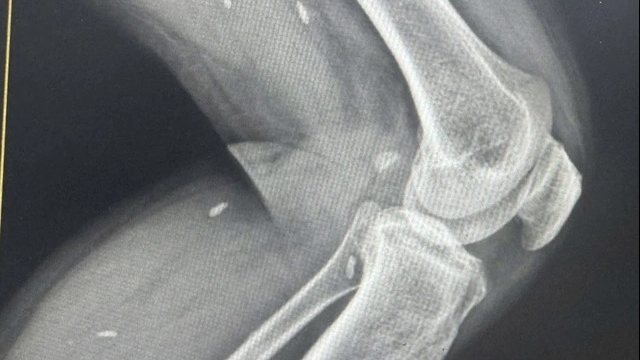

Đánh giá của các bác sĩ Khoa Y học cổ truyền, Bệnh viện Đa khoa Hòa Bình, khi vào viện cách đây 2 tháng, tay và chân của bé gái chỉ mấp máy cử động, không thể giơ lên so với mặt sàn. Bác sĩ xác định bé bị đột quỵ não.

Bác sĩ Đàm Thành Long cho biết đột quỵ là tình trạng xảy ra khi dòng máu cung cấp cho não bỗng nhiên gián đoạn do mạch máu não bị tắc (đột quỵ nhồi máu não) hoặc vỡ (đột quỵ xuất huyết não). Khi một phần não không nhận được oxy và các chất dinh dưỡng từ máu, những tế bào não sẽ dần hoại tử gây mất chức năng não bộ.